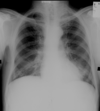

Bilateral hilar lymphadenopathy consistent with sarcoidosis